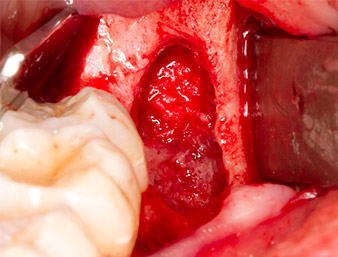

Um autogenes Material für die spätere Wundversorgung zu gewinnen, wurden mit einem piezochirugischen Instrument (Piezomed B5) gesunde Knochenspäne aus der Umgebung des Wurzelrests gewonnen (Abb. 5).

Piezomed B5

Abb. 5: Mit einem meißelförmigen piezochirurgischen Instrument (Piezomed B5) wird Knochen im Bereich der Alveole abgehoben. Dieser dient nach Entfernung des Wurzelrests als autologes Augmentationsmaterial

(vgl. Abb. 13 und 14).

Das autogene Gewebe wurde mit dem schaufelförmigen Arbeitsteil des Instruments entnommen und bis zur weiteren Verwendung in physiologischer Kochsalzlösung aufbewahrt (vgl. Abb. 13).